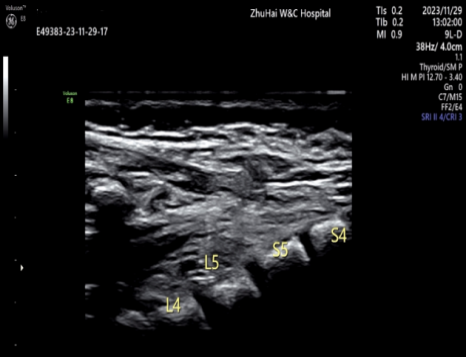

出生后,超声医生曝光了我在宝宝骶尾部的「躲藏」之路

看到这里,其实也不要过于担忧,悄悄告诉你,我也有害怕的时候。我害怕医院的影像学医生,因为他暴露了我的「秘密」通道(超声检查可以准确地显示并评估皮毛窦的形态、部位和走行方向、是否与椎管内相通、圆锥位置是否低、圆锥末端有无异常回声出现外,还可行 MRI 检查,尽可能发现合并的其他异常),更害怕外科医生,因为他一言不合就「开打」,毕竟我最大的威胁是手术。

如果产前超声检查能准确地显示并评估皮毛窦的形态、部位和走行方向、是否与椎管内相通、圆锥位置是否低、圆锥末端有无异常回声,能为宝宝出生后的治疗和随访观察提供坚实有利的依据。